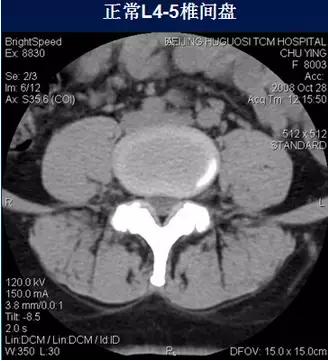

二、椎间盘膨出

椎间盘影均匀超出相应椎体边缘,轻度时CT表现为间盘后缘正常肾形凹陷消失,圆隆饱满。